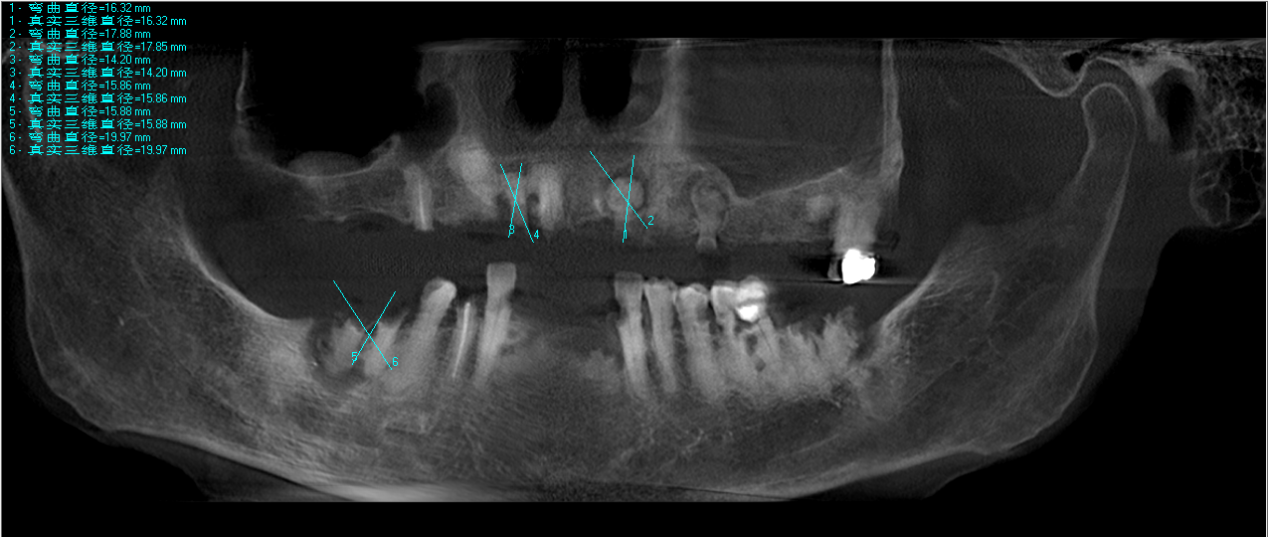

胡婆婆术前拍摄牙片

接诊后,仁爱口腔专家团队对胡婆婆进行了全面检查,发现其口内多颗残根位置复杂,部分曾接受过根管治疗,结构牢固,拔除难度较大。面对百岁高龄患者,医疗团队高度重视,特邀武汉大学口腔医院知名专家教授胡颂柏亲自主诊并制定治疗方案。经综合评估心肺功能、血压及口腔局部条件,胡颂柏认为,在严格控制手术风险的前提下,可通过分次微创拔除的方式安全实施治疗。